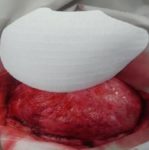

První snímky protézy

13. 12. 2012 jsem obdržela na míru vyrobenou protézu.